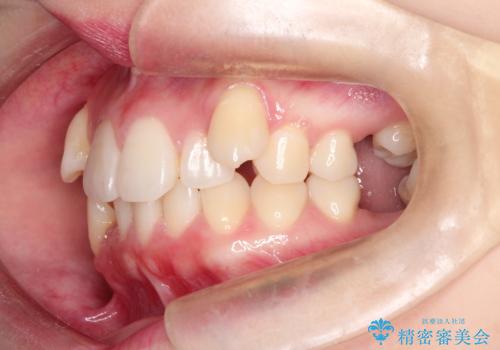

- 患者様は、下顎両側の第1大臼歯(6番)と右上6番の欠損を主訴に来院されました。

通常であればインプラントによる補綴が第一選択となる症例でしたが、患者様ご自身がインプラントを希望されなかったため、矯正治療によって欠損部の閉鎖を図る方針としました。

ワイヤー矯正を用いて、欠損部の閉鎖を目的とした後方からの歯の挺出・移動を行いました。

特に、親知らずを活用し、奥歯の噛み合わせを構築することに重点を置きました。

最終的には予定通りインプラントを使用せずに欠損部を閉鎖し、咬合も安定させることができました。